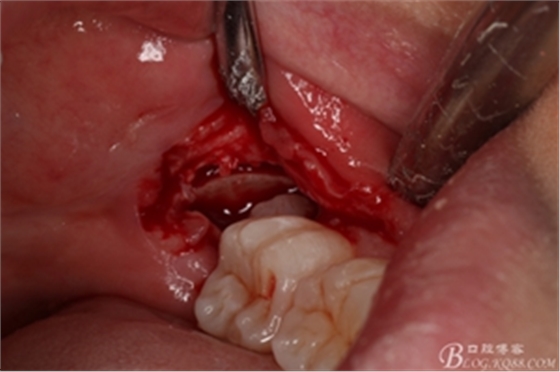

圖15.牙冠完全取出后,用微創(chuàng)丫挺取根

圖16. 38的牙根完整取出,對(duì)下頜神經(jīng)管未施加壓力